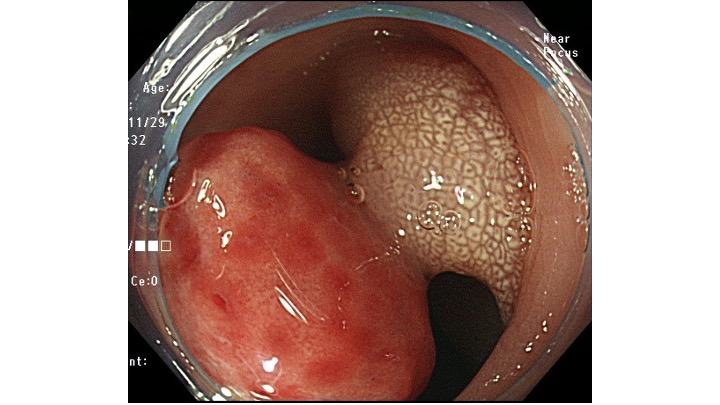

手前のひだをめくると、基部が観察され有茎性であることがわかります。